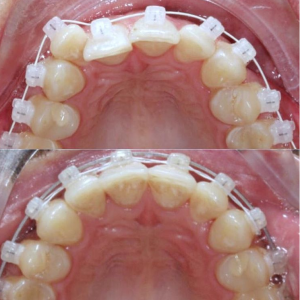

Брекеты Damon были разработаны американской компанией Ormco в 2000 году. С тех пор конструкция совершенствовалась и модернизировалась, и сегодня она представляет собой одну из самых популярных брекет-систем в мире. Благодаря самолигирующей конструкции, установка брекетов Damon проходит комфортно и безболезненно, а периодические коррекции не вызывают неприятных ощущений, как при подтягивании лигатур. Самолигирующие брекеты данного производителя бывают металлическими и керамическими. Некоторые элементы комбинированных изделий могут изготавливаться из пластика.

Как выглядят на зубах брекеты Damon? За счет легкой конструкции и модернизированных элементов даже металлические системы смотрятся аккуратнее устаревших аналогов. Комбинированные брекеты и брекеты из поликристаллического алюминия повышают эстетику улыбки за счет прозрачных замков и пазов.